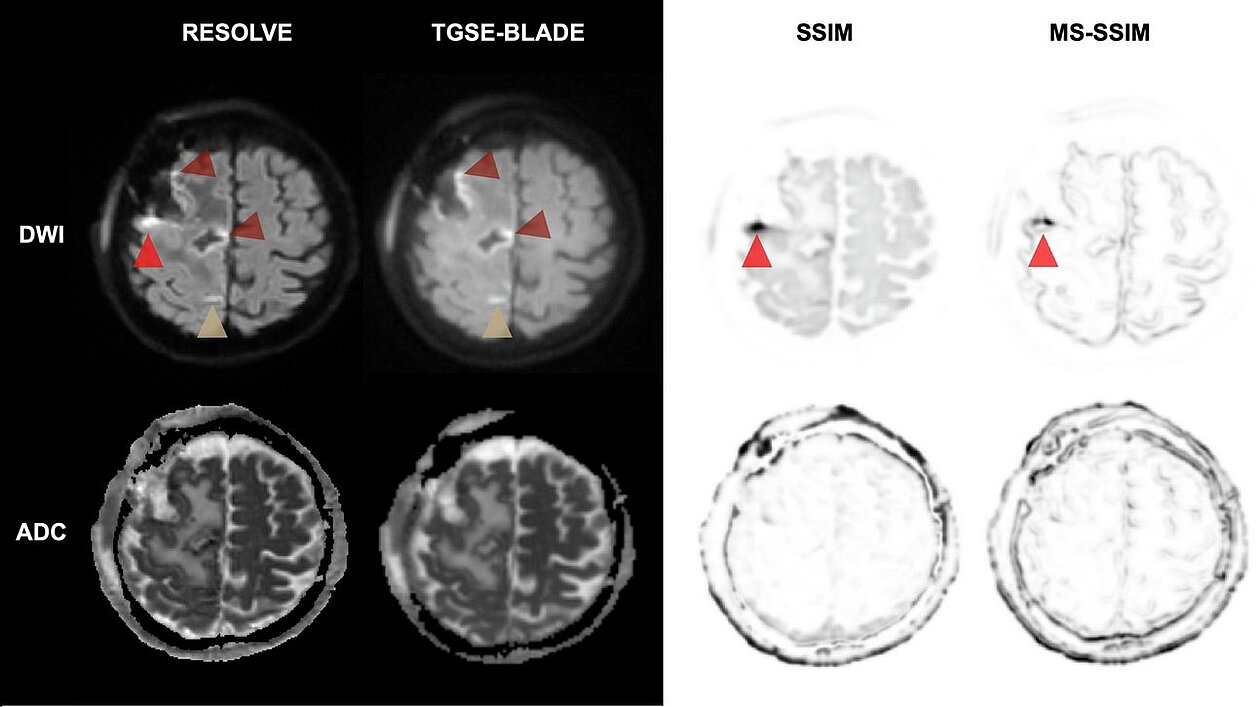

Diffusion-weighted imaging (DWI) is essential for identifying perioperative ischemic changes (minor strokes or tissue damage) near the resection site. Standard techniques like RESOLVE DWI are often impaired by geometric distortions and susceptibility artifacts caused by air-tissue interfaces after surgery. The presence of these distortions complicates the distinction between artifacts, ischemic changes, and postoperative alterations, making it challenging to obtain a clear diagnostic image.

The study found that TGSE-BLADE DWI outperformed RESOLVE in several critical areas:

- Reduced Distortion: TGSE-BLADE showed significantly fewer geometric distortions and artifacts near the resection site compared to RESOLVE (p < 0.001).

- Higher Accuracy: Measurements of the resection area on TGSE-BLADE images closely matched the T1-weighted reference scans, whereas RESOLVE showed significant discrepancies due to image warping.

- Diagnostic Confidence: Neuroradiologists reported significantly higher diagnostic confidence and better overall image quality when using TGSE-BLADE.

- Trade-offs: While RESOLVE DWI provided a slightly higher signal-to-noise ratio (SNR), the clarity and lack of distortion in TGSE-BLADE made it the superior tool for clinical assessment.